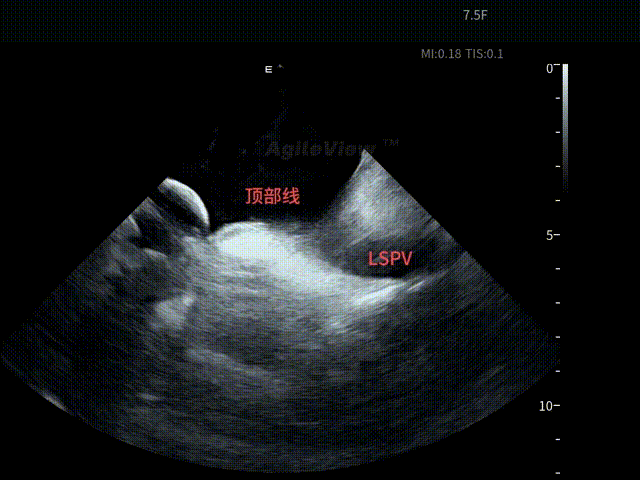

术中,基于AgileView™ 7.5Fr全球最细直径ICE导管的产品优势,周纬教授选择将ICE送入左房,以便更好地进行冷冻球囊的贴靠与位置的判断,在AgileView™ ICE实时影像的指导下, Arctic Front Advance Pro冷冻球囊导管消融导管安全进入左心房,先后完成双侧肺静脉隔离及顶部线隔离, ICE下可见导管贴靠良好,整个消融过程顺利,消融时间仅约25分钟,得益于超声设备清晰的成像质量,在顶部线隔离的时候可借助多普勒模式清晰的观察到球囊与组织的贴靠程度。 整个手术流程在ICE影像的指引下顺利完成,术中患者耐受良好,生命体征保持平稳。

顶部线第一次消融

第二次顶部线消融